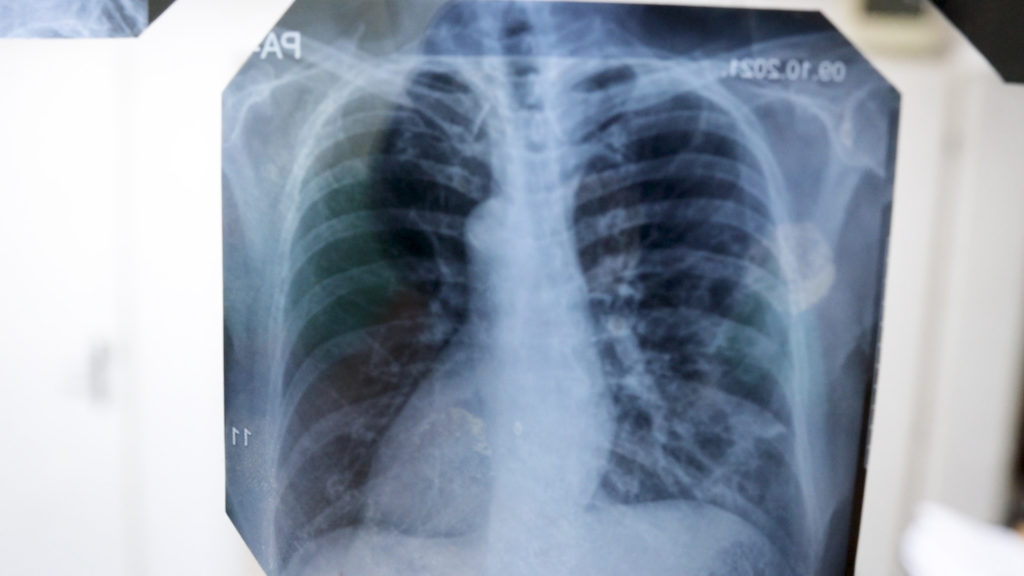

- Pulmološki pregledi: Važno je pratiti zdravlje pluća, posebno u ovim vremenima.